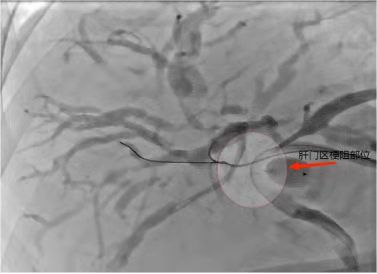

接诊的柳海华副主任医师带领团队根据患者临床表现和影像学资料,考虑患者胆管细胞癌侵犯肝门区导致胆管受阻,需尽快给病人安排手术。次日,在DSA引导下行胆道支架植入术,术中造影证实肝门区梗阻。

术中影像资料——造影肝门区梗阻